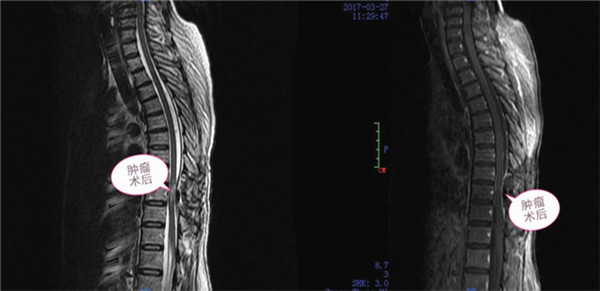

脊膜瘤血供丰富,胸椎椎管官腔较为狭窄,手术既要完全切除肿瘤又要避免损伤脊髓功能,治疗存在一定难度和风险,为此科室详细制定了手术方案,做好风险评估和应对预案,经及时而充分的术前准备,入院第三天(3月23日),手术如期进行,以张高炼主任为主刀的手术团队,术前予X线定位,并用亚甲蓝准确标记切口部位。在对患者实施麻醉后,经后正中入路,行胸9、10脊膜瘤切除术,在显微镜下仔细将正常脊髓组织与肿瘤仔细分离,操作轻、准、稳缺一不可,最终将脊膜瘤连同侵犯硬脊膜切除,并用人工硬脊膜严密修补。整个过程顺利,完整切除肿瘤,脊髓及神经保护完好。术后第一天,患者病情明显改善,皮肤感觉麻木平面明显下移,由原来的脐水平降至趾骨联合水平,双下肢肌力及大小便功能逐渐恢复;术后病理确诊脊膜瘤。术后三天,按监狱医院管理方面的要求,予转回茅桥中心医院继续康复治疗。

术后肿瘤影像